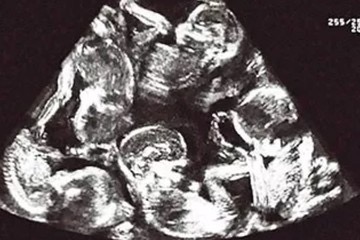

En un suceso que captó la atención de la comunidad médica internacional, una mujer egipcia se ha convertido en protagonista de uno de los casos de gestación múltiple más insólitos jamás registrados. Durante un chequeo rutinario de embarazo, la paciente, cuya identidad no ha sido revelada, fue sorprendida al descubrir que lleva nueve fetos en su útero simultáneamente.